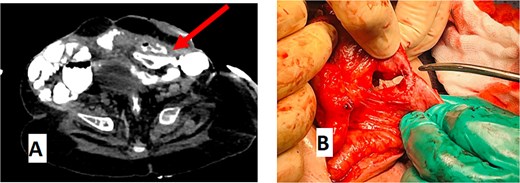

An abdominal CT scan with oral contrast revealed two ECFs: the first connected to the small bowel (Fig. 6, green arrow, corresponding to fistula number 1 in Fig. 5), and the second connected to the proximal sigmoid colon (Fig. 6, blue arrow, corresponding to fistula number 2 in Fig. 5). Furthermore, an enteroenteric fistula between the ileum and rectosigmoidal junction was noted (Fig. 7, red arrow).

CT abdomen with oral contrast showing two enterocutaneous fistulas. Green arrow: fistula connected to the small bowel. Blue arrow: fistula connected to the proximal sigmoid colon.

(A) CT abdomen with oral contrast showing enteroenteric fistula. The red arrow indicates a fistula between the ileum and the rectosigmoid junction. (B) Gross appearance of the enteroenteric fistula.